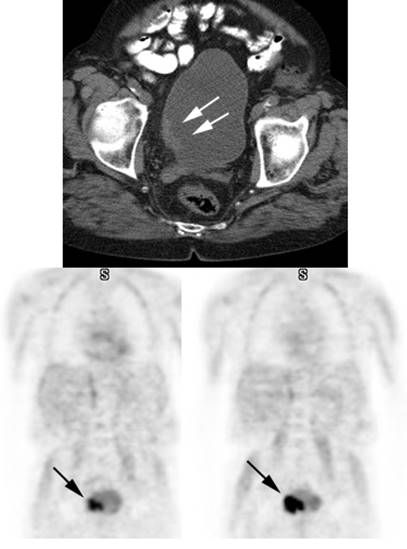

Figure 7 - Bladder cancer: Despite urinary excretion

of the radiotracer, this patients bladder cancer

(white arrows) is readily identified on the PET scan (black arrows). In

general, however, urinary excretion of FDG limits evaluation of urinary tract

malignancy